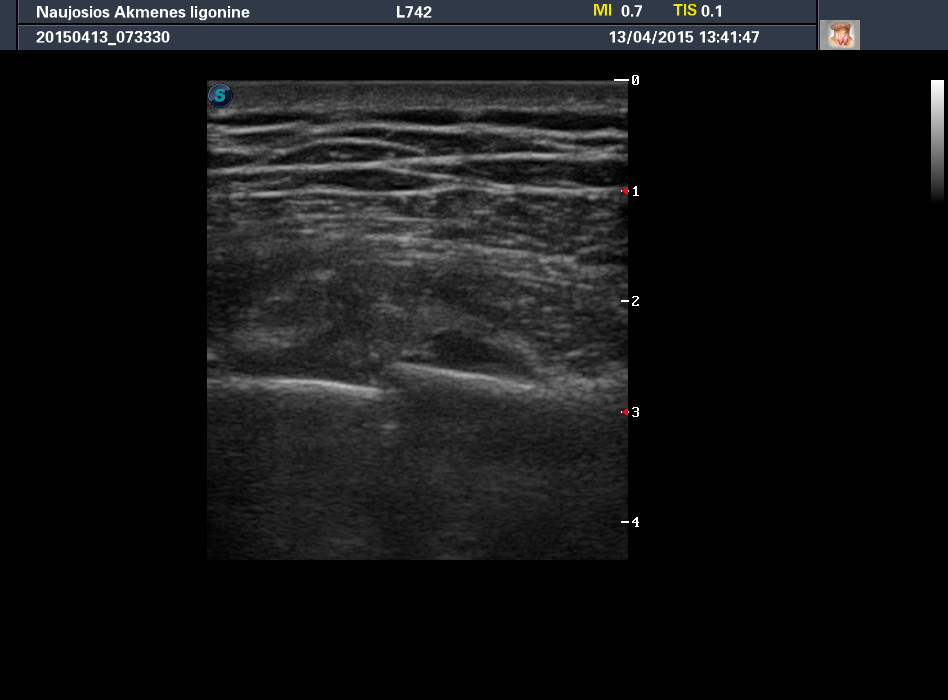

Мужчина средних лет.

Упал с лестницы. Клинически есть перелом ребер. На рентгене картина непонятная. Направлен на УЗИ для подтверждения перелома.

Продольное сканирование 12-го ребра.

Есть, похоже.

Прицельный рентгеновский снимок опять сомнительный.

Что можно сделать при передне-заднем смещении костей при рентгенографии? Ситуация непростая, так как случай страховой, рентгенолог на больничном. Я отписал перелом по данным УЗИ на веселуху местным врачам, но не уверен что этого будет достаточно страховым.